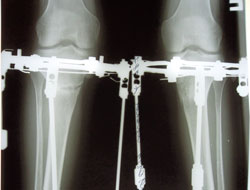

Дата операции 10.06.2014г.

Дата снятия 30.09.2014г.

Срок лечения 110 дней.